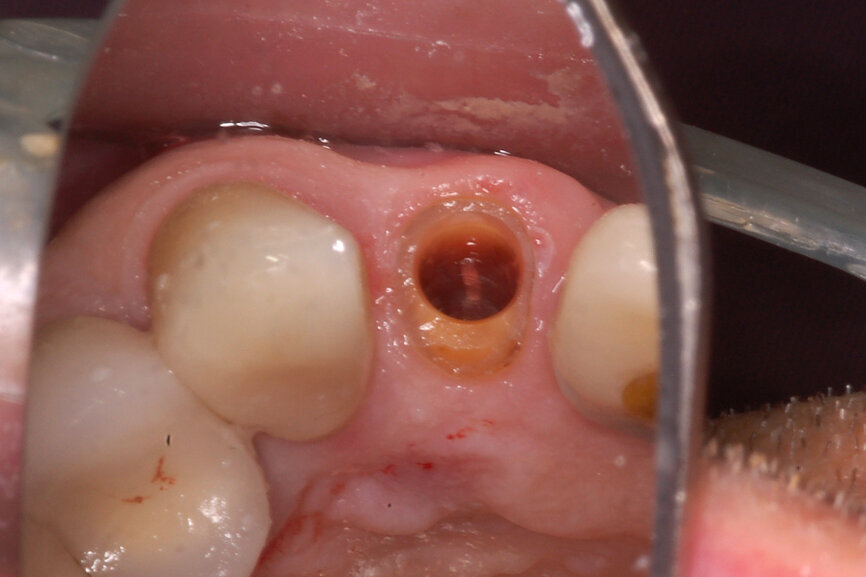

Fig. 12a: A post fracture presenting in the left central incisor, requiring extraction.

Fig. 12b: The occlusal view illustrated the cervical tissue volume and contours.

A 62-year-old male patient presented with a hopeless prognosis for a post fracture in the left central incisor requiring extraction (Figs. 12a & b). The preoperative periapical radiograph revealed an existing implant supporting a metal–ceramic restoration for the adjacent region #11 (Fig. 13). The CBCT (CS 9600, Carestream Dental) cross-sectional image revealed a favourable preoperative condition relating to the trajectory of the endodontically treated root to the alveolus for a PET procedure (Fig. 14a). Using the native Carestream 3D Imaging software, a simulated implant and abutment projection was positioned within the available bone to avoid the root fragment (Fig. 14b).